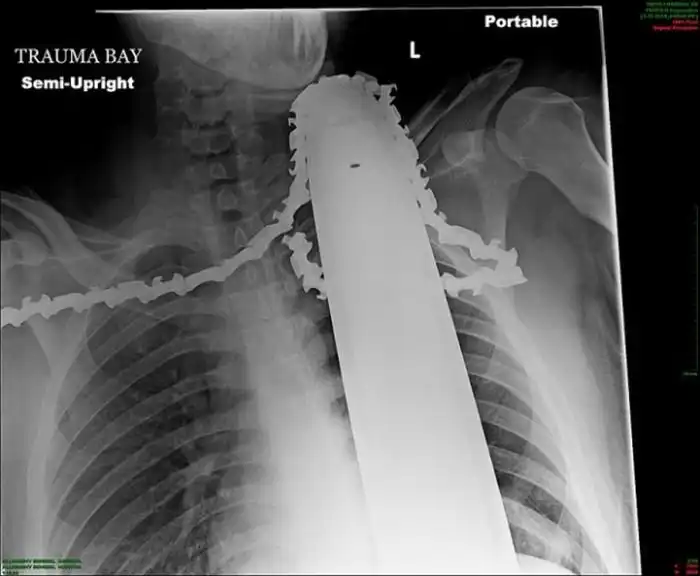

Жуткие рентгеновские снимки

Порой даже не верится, с какими странными и необычными повреждениями в травматологию могут поступить пострадавшие. Всю эпичность профессии врачей травматологии могут с легкостью подтвердить рентгеновские снимки.